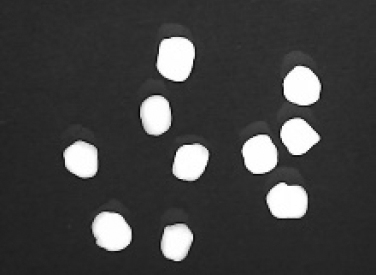

Disintegration was evaluated at room temperature under static conditions. The camera captured images every 30 s ( Table 9), illustrating that MCC pellet X3 with mannitol and PEG 400 did not disintegrate. Within 120 s, cracks appeared in P5 pellets containing mannitol, PEG, and PPXL. As seen in the C4 pellets, they begin to explode into many fragments within 30 s. Moreover, the CP12 pellets containing PEG 400, mannitol, CCS, and PPXL began to explode into many loosely linked particles after 60 s, which quickly separated under the oscillating motion of the USP disintegration equipment. The photographs are compatible with the results mentioned above for the USP disintegration device. When the temperature was increased to 37°C, the disintegration caused the split into tiny fragments.

Table 9. Camera capture of pellet disintegration at different time intervals.

Pellet # 0 sec. 30 sec. 60 sec. 90 sec. 120 sec.

CP12c9c3975f-9288-4951-a800-a8e9fc463382_GRA73.gif c9c3975f-9288-4951-a800-a8e9fc463382_GRA74.gif c9c3975f-9288-4951-a800-a8e9fc463382_GRA75.gif c9c3975f-9288-4951-a800-a8e9fc463382_GRA76.gif c9c3975f-9288-4951-a800-a8e9fc463382_GRA77.gif